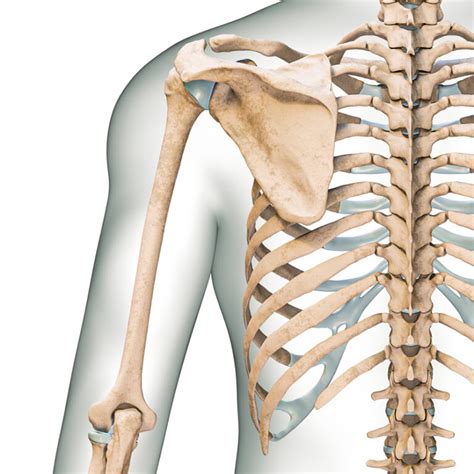

Hey guys, let’s dive into the world of Oscifit 500mg , a supplement that’s been making waves when it comes to keeping our bones strong and healthy. We all know that strong bones are crucial for pretty much everything we do, from running around and playing sports to just standing up straight. As we get older, or sometimes even due to lifestyle choices, our bone density can take a hit, leading to issues like osteoporosis. That’s where supplements like Oscifit 500mg come into play, aiming to give our bodies that extra support they need. In this article, we’re going to break down what Oscifit 500mg is, how it works, who might benefit from it, and some important things to keep in mind. We want to make sure you’re well-informed so you can make the best choices for your well-being. So, grab a cuppa, get comfy, and let’s explore how Oscifit 500mg can be a part of your journey to robust bone health. We’ll cover everything from its core ingredients to practical advice, ensuring you get a comprehensive understanding. Our goal is to provide clear, valuable information that empowers you to take proactive steps towards maintaining and improving your skeletal system’s strength and resilience. Remember, taking care of your bones is a lifelong commitment, and understanding your options is the first step.

Let’s get down to the nitty-gritty of how Oscifit 500mg actually helps keep your bones in tip-top shape. The primary mechanism, guys, is straightforward: providing your body with the essential building material it needs. Our bones are constantly undergoing a process called remodeling, where old bone tissue is broken down and new bone tissue is formed. This cycle is crucial for maintaining bone strength and repairing micro-damage. Calcium is, without a doubt, the star ingredient here. Oscifit 500mg delivers a significant amount of calcium, which is directly incorporated into the bone matrix, making them denser and stronger. But it’s not just about adding bricks; it’s about building a solid structure. This is where the synergy with other potential ingredients, like Vitamin D, comes into play. As we touched upon, Vitamin D is absolutely critical for enabling your intestines to absorb calcium from the food you eat and from the supplement itself. Without adequate Vitamin D, a large portion of the calcium you consume might just pass through your system unused. So, Oscifit 500mg, especially when formulated with Vitamin D, ensures that the calcium provided is actually bioavailable – meaning your body can effectively use it. Furthermore, adequate calcium and Vitamin D levels help to balance the hormones that regulate calcium, like parathyroid hormone. This balance is key in preventing the body from leaching calcium from the bones to maintain critical blood calcium levels. For women, especially post-menopause, and for older adults in general, bone loss can accelerate due to hormonal changes. In these cases, a consistent intake of calcium, supported by Vitamin D, can help slow down this rate of bone resorption (breakdown) and promote bone formation, thereby helping to maintain bone mineral density. Think of it as giving your body the resources it needs to keep pace with the natural process of bone breakdown, or even to outpace it slightly, leading to stronger, more resilient bones that are less prone to fractures. It’s all about providing the right materials and ensuring they get to where they need to go, effectively and efficiently.

To wrap things up, Oscifit 500mg stands out as a valuable ally in the ongoing quest for strong, healthy bones. We’ve explored how its core component, calcium, is fundamental to bone structure and remodeling, and how crucial supporting nutrients like Vitamin D can be for optimal absorption and utilization. Whether you’re a woman navigating menopause, an older adult concerned about age-related bone density changes, someone managing diagnosed bone conditions, or simply looking to ensure adequate dietary intake, Oscifit 500mg offers a accessible way to bolster your skeletal system. Remember, it’s not just about popping a pill; it’s about integrating this support into a holistic approach to health that includes a balanced diet, regular exercise (especially weight-bearing activities), and sufficient Vitamin D exposure. We’ve also highlighted the importance of correct dosage, taking it with food, and considering potential side effects and interactions. The key takeaway is to approach supplementation intelligently and always consult with your doctor or a qualified healthcare professional . They can help personalize your calcium and Vitamin D intake, ensuring Oscifit 500mg fits safely and effectively into your unique health profile. By doing so, you’re not just taking a supplement; you’re making an informed investment in your long-term mobility, independence, and overall quality of life. Here’s to building and maintaining a strong foundation for years to come with Oscifit 500mg and informed choices!